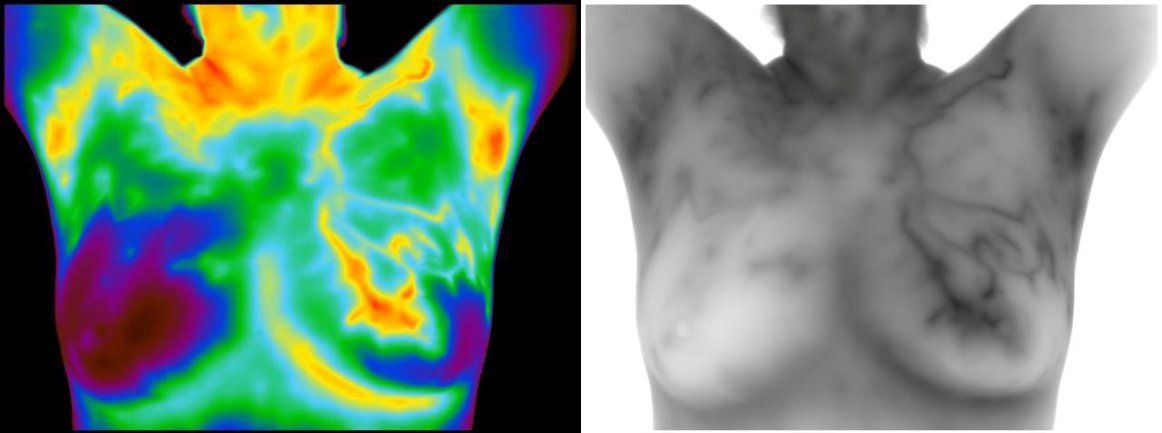

Do you get an annual breast screening? Most patients contact us because they have found a lump in their breast or they know someone who has cancer. These people begin doing research or they want to be proactive with their health. Through these efforts, they discover the benefits of our valuable screening tool. At Flow Well, we offer medical thermography screenings for possible cancer detection, but it is ideally used for preventing future issues. Thermography uses an infrared camera to take a series of images of your body. These images detect the physiology of your body. Our interpreting doctors analyze the heat signatures in your images. You can tell from our reporting what is unusually hot or unusually cold. From there, you will work with your doctor or other wellness professionals to balance things out for your follow up screening. Thermography is most well-known for breast thermography but it is beneficial for the entire body for men, women, and children.

Most patients use thermography to assess their health. Thermography is considered an adjunctive screening tool to anatomical testing. There is no contact, no radiation, and no compression with infrared imaging. During these times it is more important now than ever before to analyze your health. When you get a thermography screening that shows optimal balance in the body, your immune system is then ready to tackle anything that comes your way.